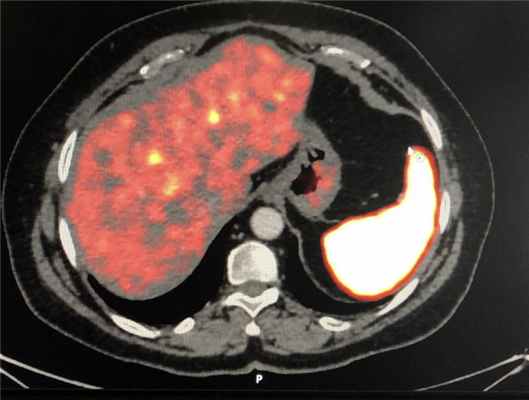

Метастазирование надпочечников Надпочечник является одним из наиболее распространенных мест для метастазирования различных злокачественных опухолей. По данным вскрытия, первичные злокачественные опухоли, отличные от надпочечников, обнаруживаются в надпочечниках с метастазированием, составляющим от 8 до 38%. Первичные злокачественные опухоли, отличные от надпочечников. Если односторонний надпочечник имеет объемное поражение, частота поражения составляет от 32% до 73%, а диаметр надпочечников составляет> 3 см. Вероятность злокачественного образования составляет от 43% до 100%, а диаметр составляет < 3 см менее вероятно, чтобы быть злокачественными, а метастазы в надпочечниках в основном двусторонние. Первичные злокачественные опухоли включают рак молочной железы, рак легкого, почечно-клеточный рак, меланому и лимфому. Для выявления первичного необходимо обследование изображения. Опухоль и другие метастатические опухоли, КТ или биопсия тонкой иглой под ультразвуковым контролем полезны для окончательного диагноза, но должны выполняться после исключения феохромоцитомы.

Аденомы надпочечников обычно являются доброкачественными новообразованиями мезотелиального происхождения. Встречаются у мужского и женского пола в одинаковых соотношениях. Есть случаи, когда аденоматоидные опухоли встречаются в печени, кишечной брыжейки, поджелудочной железе и т.д. Первая аденоматоидная опухоль была описана в 1945 году Голденом. За последние годы объемные образования надпочечников стали диагностировать все чаще. Это связано с модернизацией диагностических технологий. На сегодняшний день, благодаря КТ, МРТ, ПЭТ исследованиям злокачественные образования своевременно обнаруживается на ранних стадиях. В настоящей статье рассматривается клинический случай образования надпочечника.

ПЭТ-КТ с галием (68Ga-DOTATATE и 68Ga-DOTANOC),

ПЭТ-КТ с глюкозой (ФДГ)